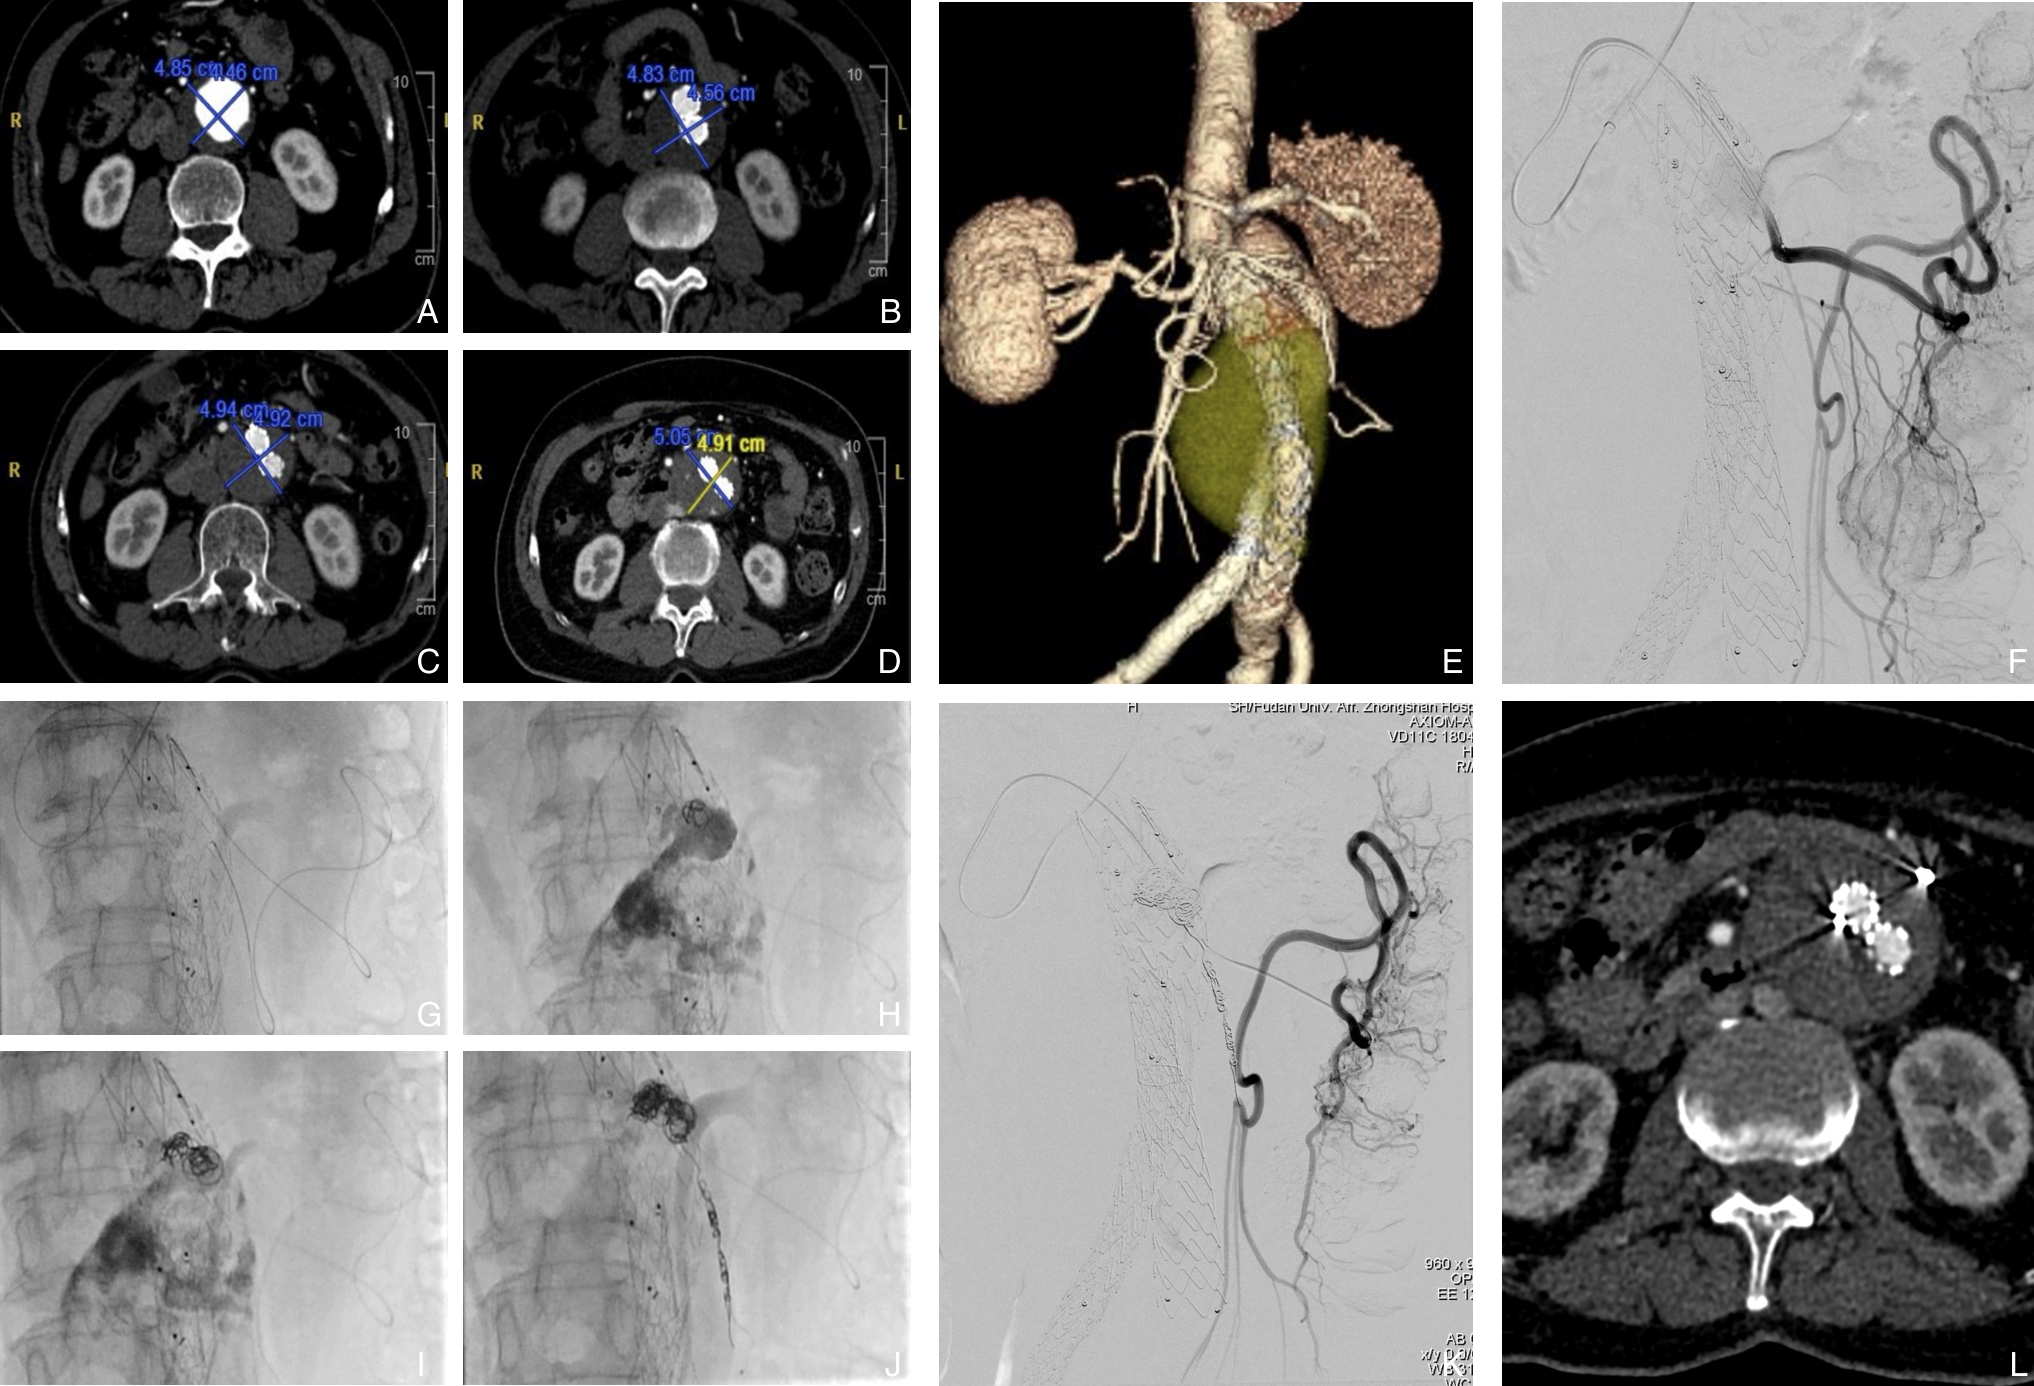

2025, 34(12):2568-2576. doi: 10.7659/j.issn.1005-6947.250354

摘要:背景与目的 Ⅱ型内漏是腹主动脉瘤腔内修复术(EVAR)后最常见的并发症之一,与术后瘤体持续增大及再干预密切相关。肠系膜下动脉(IMA)是Ⅱ型内漏的重要血流来源,其预防性栓塞的临床价值尚存争议。本研究旨在评估预防性IMA栓塞对EVAR患者术后内漏、瘤体变化及再干预的影响。方法 回顾性分析2022年1月—2024年1月接受EVAR治疗的肾下腹主动脉瘤患者,根据是否行预防性IMA栓塞分为栓塞组和非栓塞组。比较两组患者术前基线资料、围术期情况及随访结局。采用Kaplan-Meier法分析无内漏生存率、无Ⅱ型内漏生存率、免于瘤体增大生存率及免于再干预生存率。结果 共纳入233例患者,其中62例接受预防性IMA栓塞。栓塞组与非栓塞组在术前基线特征及瘤体解剖学参数方面差异无统计学意义(均P>0.05)。平均随访(19.6±9.7)个月。与非栓塞组相比,栓塞组术后2年无内漏生存率(93.55% vs. 74.53,P=0.027)、无Ⅱ型内漏生存率(95.11% vs. 80.02,P=0.043)、无IMA相关Ⅱ型内漏生存率(100.0% vs. 85.26,P=0.019)及免于瘤体增大生存率(94.27% vs. 81.96,P=0.026)均明显提高。两组在术后再干预率方面差异无统计学意义(P=0.388)。结论 预防性IMA栓塞可显著降低EVAR术后内漏,尤其是IMA相关Ⅱ型内漏的发生,并有助于抑制瘤体增大,但对降低再干预率的作用尚不明确,仍需大样本、长期随访研究进一步验证。